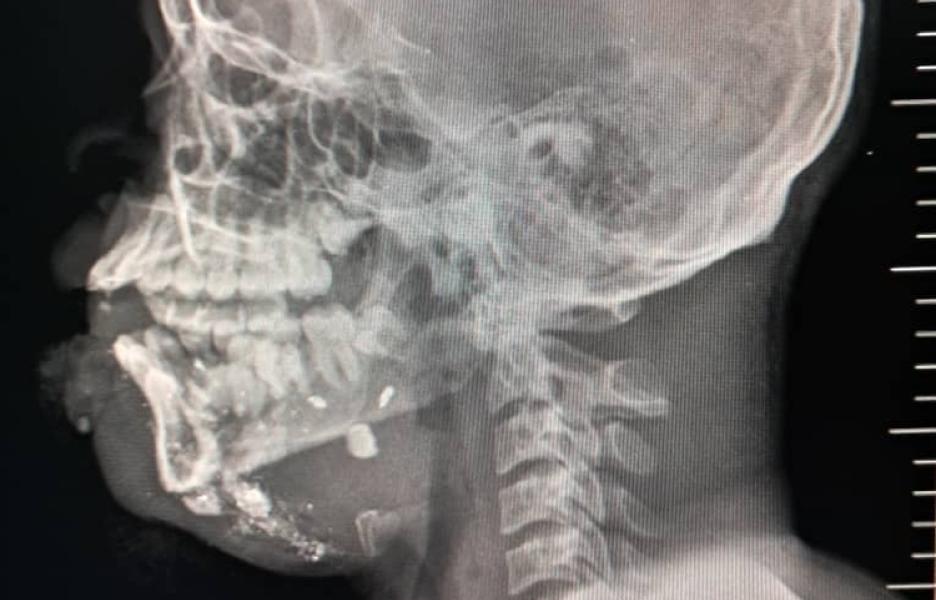

Esther*, de 16 años, fue alcanzada por una bala perdida cuando iba a comprar comida al mercado. Su fémur quedó gravemente dañado. Tras una cirugía reconstructiva, pasó dos meses en el Hospital de MSF de Tabarre. © MSF